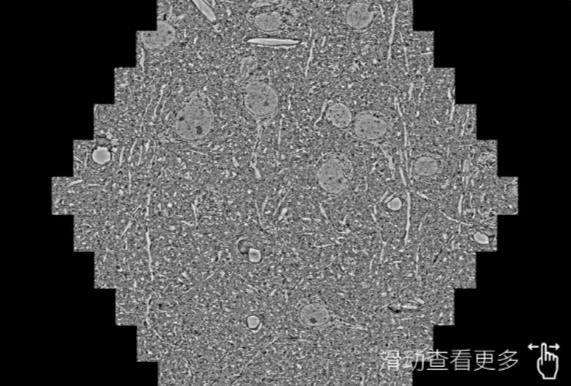

鼠脑切片。左图使用延安蔡司延安扫描电镜MultiSEM706对165μmx143pm面积区域成像,耗时仅需1.5秒。右图为鼠脑切片中30μm区域放大效果。样品由芝加哥大学B.Kasthuri提供。

使用蔡司高速延安扫描电镜MultiSEM对1mm²人脑皮层组织进行高分辨成像,并对其中的各种细胞结构进行三维重构分析。左图展示了2x3mm²组织平面中锥体神经元的三维重构效果。右图显示了局部体积神经元三维重构。图像由哈佛大学chtman实验室提供,渲染图由D. Berger 制作。